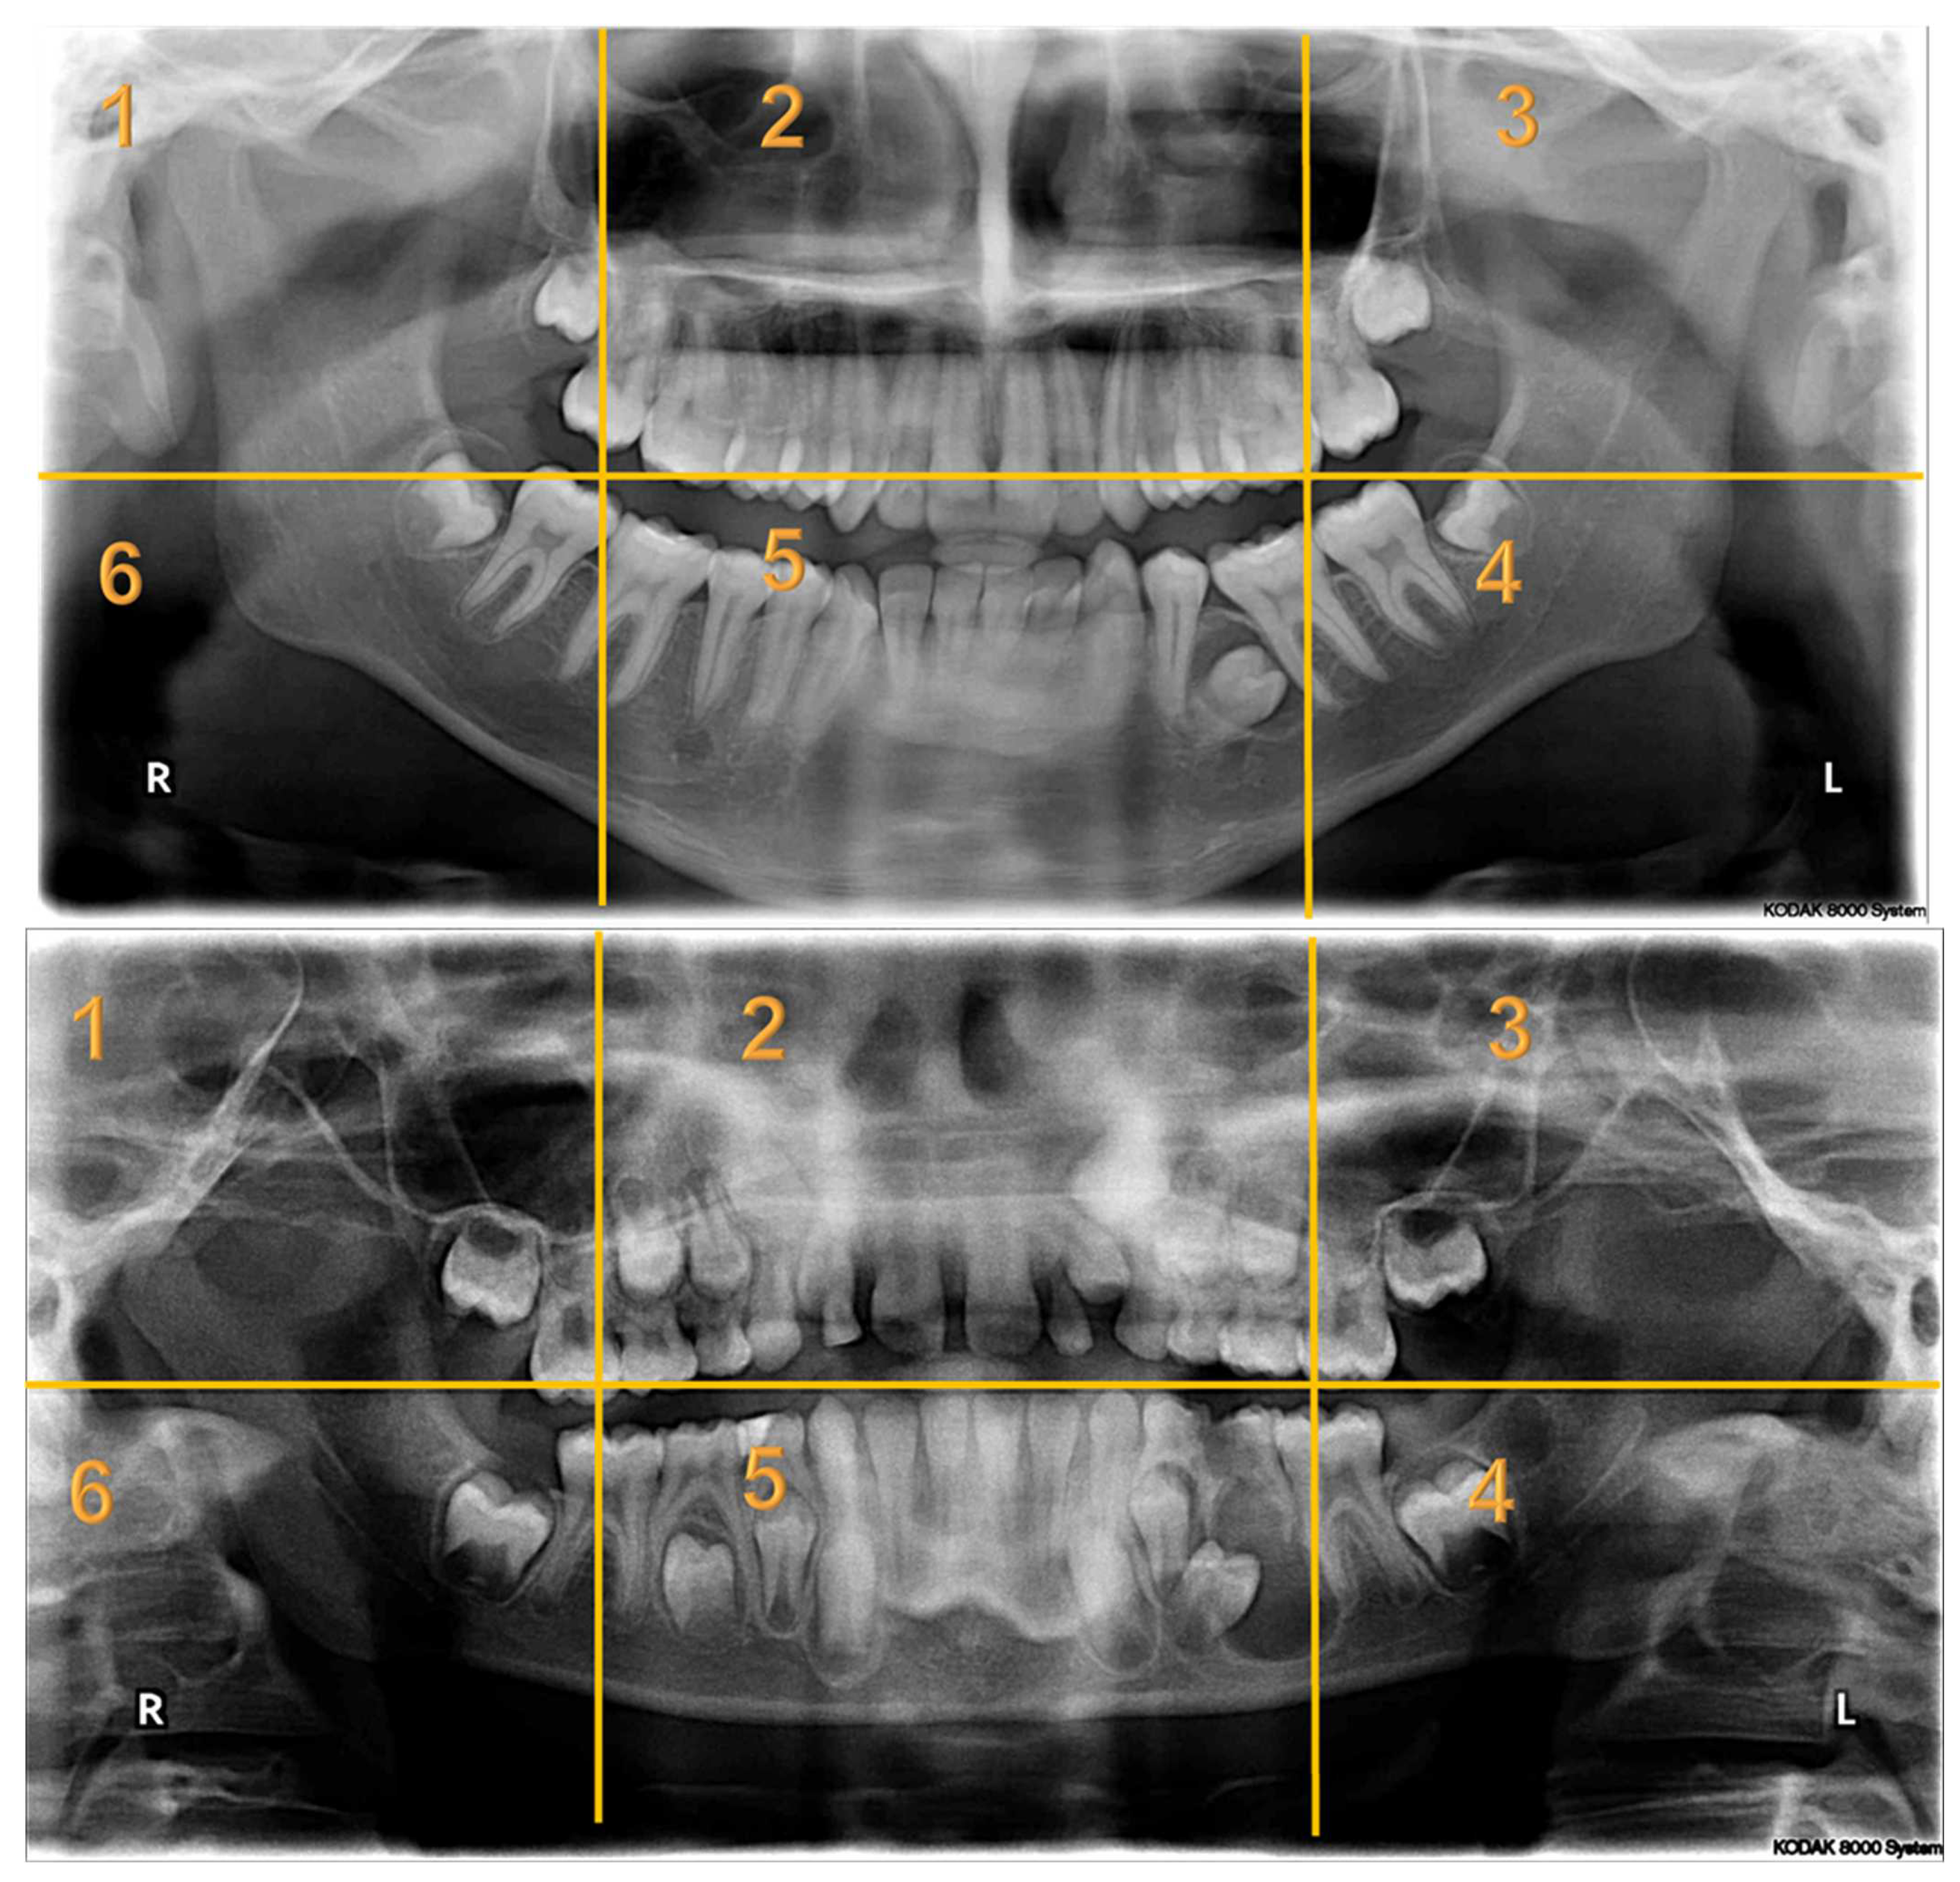

Appendix A. Radiographs Included in the Study

- Each panoramic radiograph displayed will be divided into sextants by yellow lines.

| Radiographs with Abnormalities | Number of Sextants Involved | Number of AOI a | Number of Participants | Total Recorded Observation b |

|---|---|---|---|---|

| Radiograph 1 | Multiple | 3 | 30 | 90 |

| Radiograph 2 | Multiple | 8 | 30 | 240 |

| Radiograph 3 | Single | 2 | 30 | 60 |

| Radiograph 4 | Single | 2 | 30 | 60 |

| Radiograph 5 | Single | 1 | 30 | 30 |

| Radiograph 6 | Single | 1 | 30 | 30 |

| Radiograph 7 | Single | 1 | 30 | 30 |

| Overall Observations | 540 |